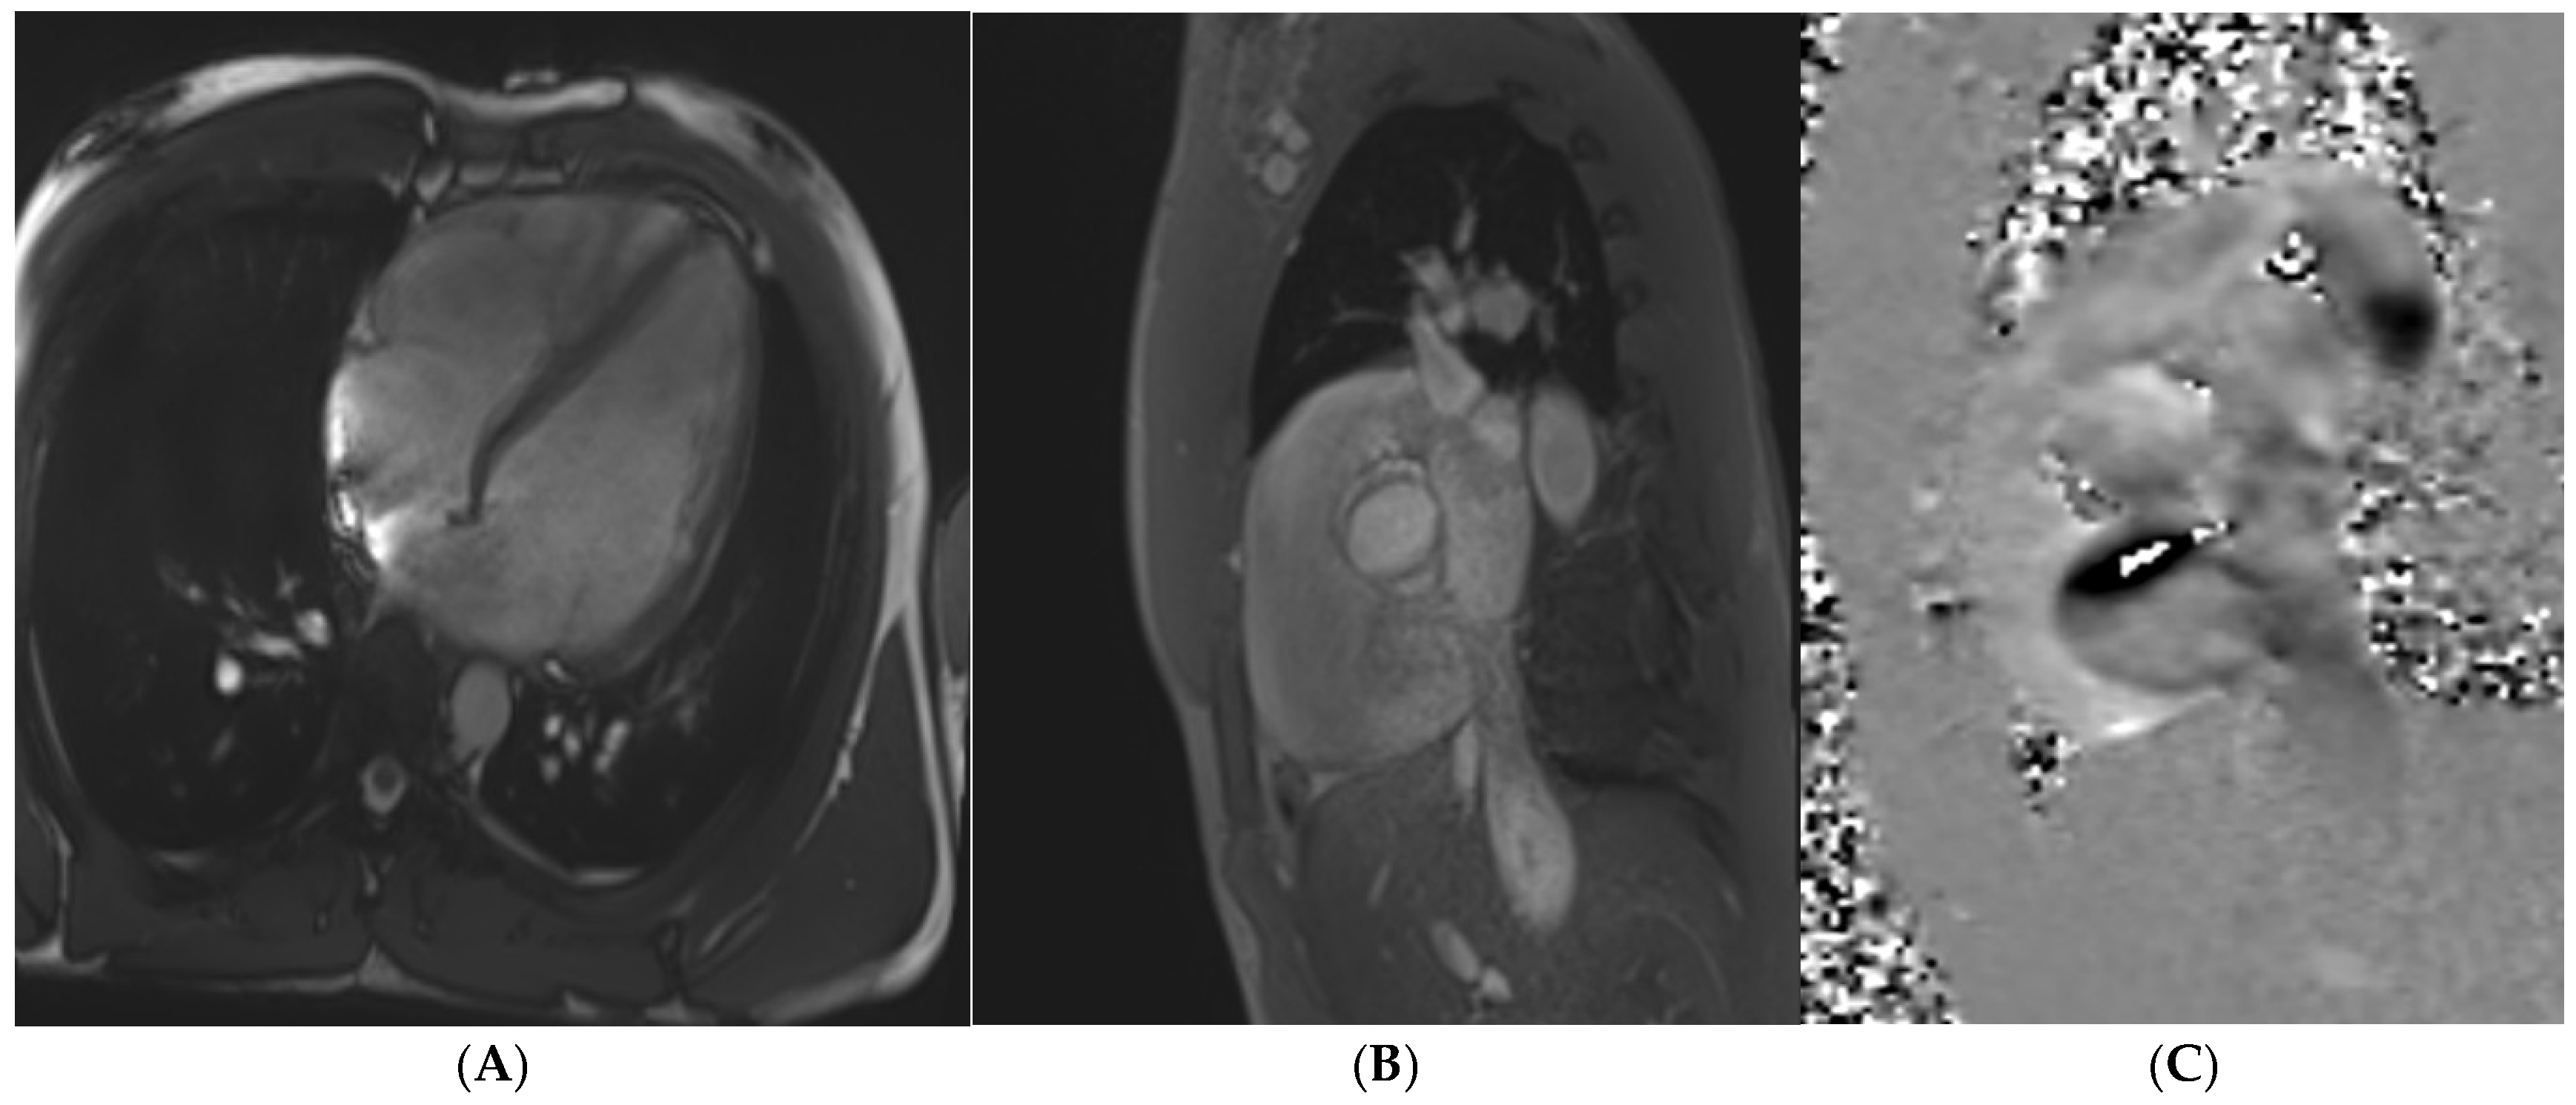

14. Other Valvular Heart Disease

6. Pre-Clinical Cardiomyopathy

13. Bicuspid Aortic Valve and Aortopathy